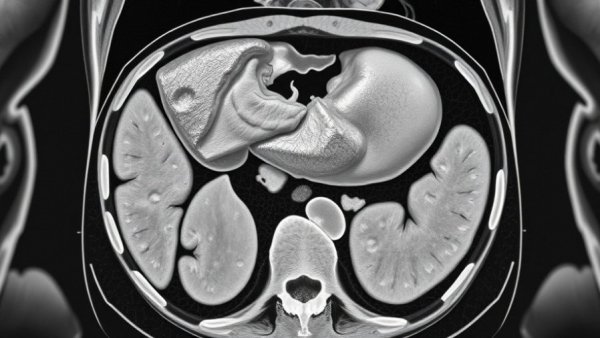

Grayscale CT scan highlighting biomarkers for early detection of pancreatic cancer.

Pancreatic cancer is often diagnosed too late due to symptoms that emerge in advanced stages, resulting in a disheartening five-year survival rate of just 13%. However, breakthrough research from Indiana University's Fairbanks School of Public Health has pinpointed a set of biomarkers that show promise in enhancing early detection of this notoriously aggressive disease. Led by Dr. Jianjun Zhang, this collaboration aims to identify pancreatic cancer at its most treatable stage, a crucial aspect that could change the grim survival statistics.